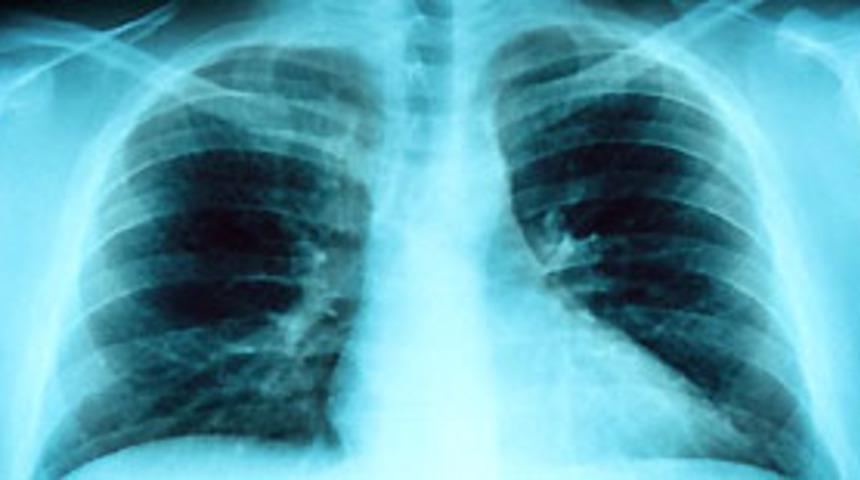

Türkiye'de yaklaşık 3 milyon kronik akciğer hastasının bulunduğu ve hastalık için en önemli risk faktörünün sigara kullanımı olduğu bildirildi.

Sağlık Bakanlığı, vatandaşları ölümlere yol açan Kronik Obstrüktif Akciğer Hastalığı (KOAH) konusunda uyardı. Tedavi Hizmetleri Genel Müdürlüğü'nden yapılan açıklamada, akciğerlerdeki hava yollarının daralmasına bağlı olarak insanların nefes almalarını zorlaştıran KOAH'ın, en tehlikeli akciğer hastalıkları arasında yer aldığına dikkat çekildi. Açıklamada, Türkiye'de akciğer hastalıkları nedeniyle kaybedilen hastaların yüzde 20'sini KOAH'lıların oluşturduğu vurgulanarak, hastalığın oluşumunda en önemli ve önlenebilir tek nedenin sigara olduğu kaydedildi. Sigara tiryakilerinin potansiyel KOAH adayı olduğu bildirilen açıklamada şu uyarılara yer verildi:

KOAH'ın nefes darlığı, öksürük, balgam çıkarma, göğüste tıkanma, hırıltılı solunum ve morarma gibi yakınmalarla ortaya çıktığı belirtilen açıklamada, hastalığın en önemli belirtisinin, kişinin yılın en az 3 ayında balgamlı öksürmesi ve bu durumun en az 2 yıl tekrarlaması olduğu bildirildi. Hastalığın aniden başladığı ifade edilen açıklamada, kişiyi kolayca terk etmeyen KOAH'ın giderek artan bir seyir izlediği ve ölümlere yol açan önemli bir hastalık olduğu kaydedildi. Açıklamada, öksürük, balgam artışı ve nefes darlığına neden olan KOAH'ın, aradan geçen yıllar içinde kişide kalıcı işgücü kaybına yol açarak kişiyi başkalarının desteğine bağımlı hale getirdiği dile getirildi.